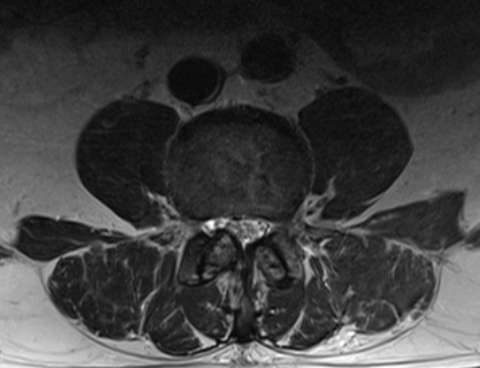

腰椎すべり症/ 脊柱管狭窄症

主訴 腰痛 左下肢痺れ

視診 左椎間板症状様疼痛回避姿勢

整形外科テスト SLRテスト 20°左(+++)

筋力検査 左長母趾伸筋低下

その他 輻輳反射 左低下